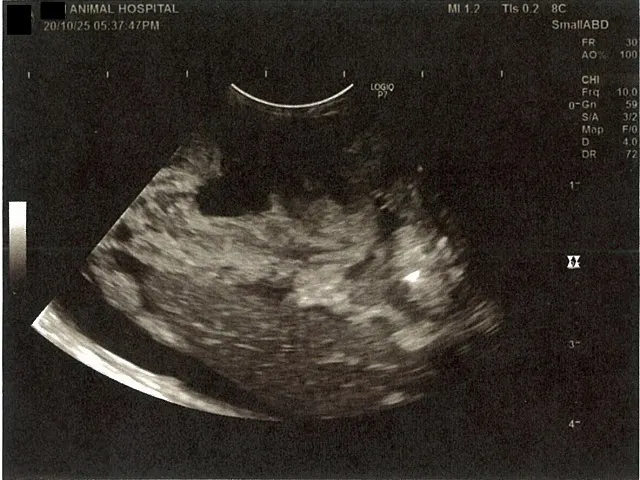

右腎臓周りに腹水が確認できるエコー写真

心臓のみ腹水が確認できないエコー写真